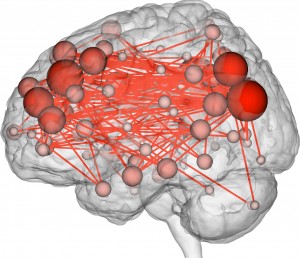

The method of analysis was novel, in part, because the team deviated from traditional methods of analyzing functional MRI (fMRI), a technique used to measure the activity and understand the function of different brain regions. Past fMRI studies had been concerned with measuring activity changes in single regions. Instead, the researchers studied activity levels throughout the entire brain. They divided the brain into a network of 263 nodes and monitored how closely activity levels between each node corresponded with one another. If two nodes were more active at the same time, then those regions were considered “functionally connected.”

Different regions in the brain function as a network, coordinating their activity; what surprised the researchers was the discovery that these connectivity profiles are highly individualized. This had not been shown in previous fMRI studies, which would average fMRI data across a large number of scans, thereby missing this personalization of patterns in brain activity.

The connectivity profiles, which resemble QR codes in appearance, can do more than simply differentiate individuals. They can also predict, with a certain degree of accuracy, levels of fluid intelligence: an individual’s capacity to solve problems and think logically.